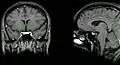

Гипофиз на сагиттальном и корональном срезах МРТ с контрастным усилением.